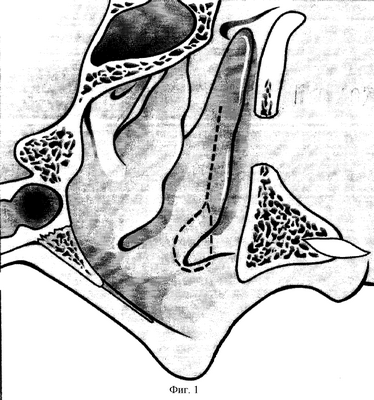

1 этап: скальпелем рассекается слизистая у переднего конца нижней носовой раковины, и кзади, отступив от основания 2-3 мм до кости. Тонким долотом мобилизуется вся раковина, оставаясь фиксированной к латеральной стенке полости носа в задних отделах (сосудистая ножка согласно топике кровоснабжения) (фиг.1).